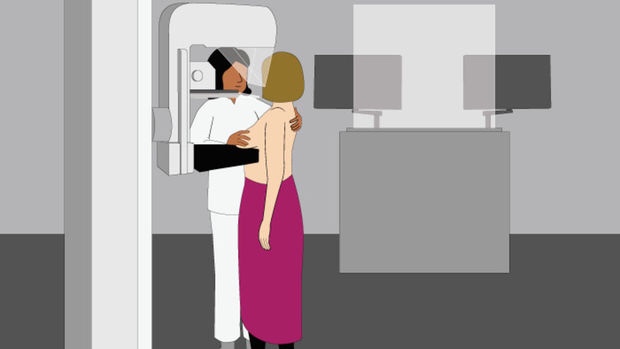

Er was een wachttijd bij de mammapolie, maar dat vond ik niet erg. Onze (schoon)moeder konden we nu in alle rust en kalmte begeleiden naar en tijdens de uitvaart. De dag erna stond mijn date gepland met de tietenplet-machine! Ik zag er tegenop hoor. Het leek mij niets, dat gesjor aan je borst door een vreemde dame. Maar wat moet, dat moet.

Het viel uiteindelijk mee! Het is zeker niet prettig maar echt super pijnlijk was het nou ook weer niet: Je staat ongemakkelijk. Je borst wordt op zo’n ‘tafeltje’ gekleid en dan komt de plexiglas plaat erop. Handmatig geeft de verpleegkundige nog een kleine extra draai aan de plaat en dan gaat de ‘kopieer-machine’ er bovenlangs.

[…] maar gelukkig bleek het een onschuldige cyste (een met vocht gevulde holte). Ik schreef er een blog over en beschreef hoe een mammografie nou in zijn werk […]